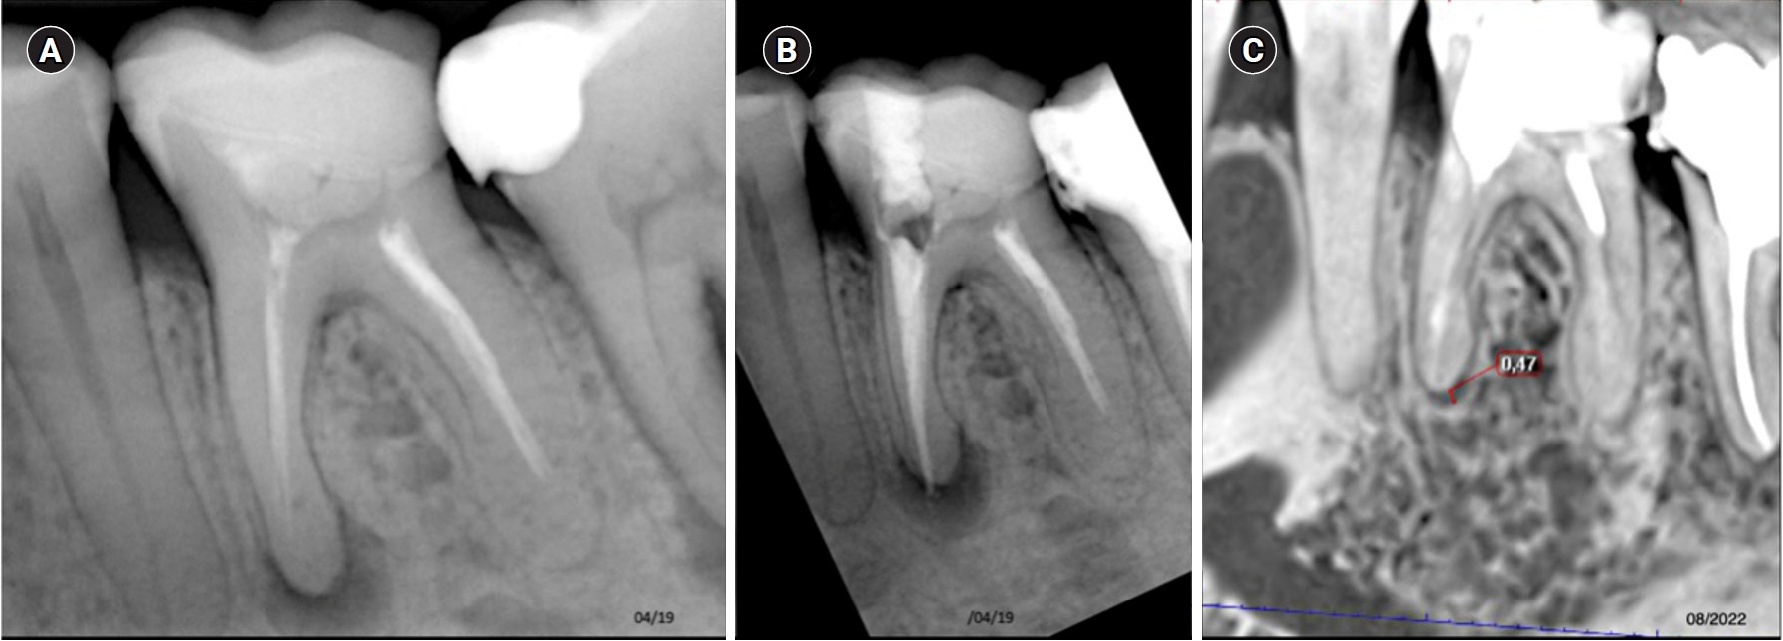

This image shows tooth 37 diagnosed with pulp necrosis with a chronic periapical abscess. (A) Diagnostic X-ray. (B) Immediate after obturation. (C) Tomographic control where complete healing is evident after 45 months.